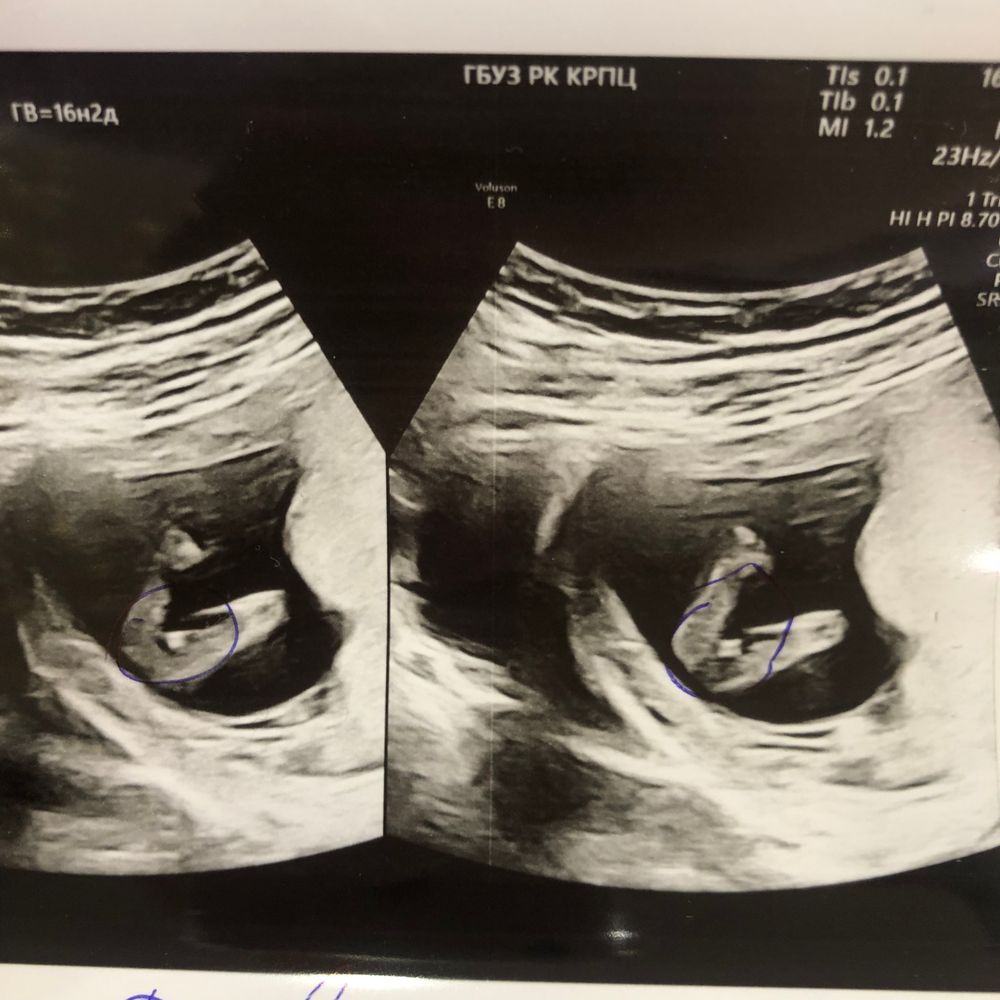

Пророчат девочку , но вот этот 1%)

Все привет мне пророчат доченьку , у кого есть опыт в узи , срок 13,2 ❤️🤞 мы конечно будем рады любому исходу но дочка как приятный бонус 😍🍀 всем заранее спасибо ☺️